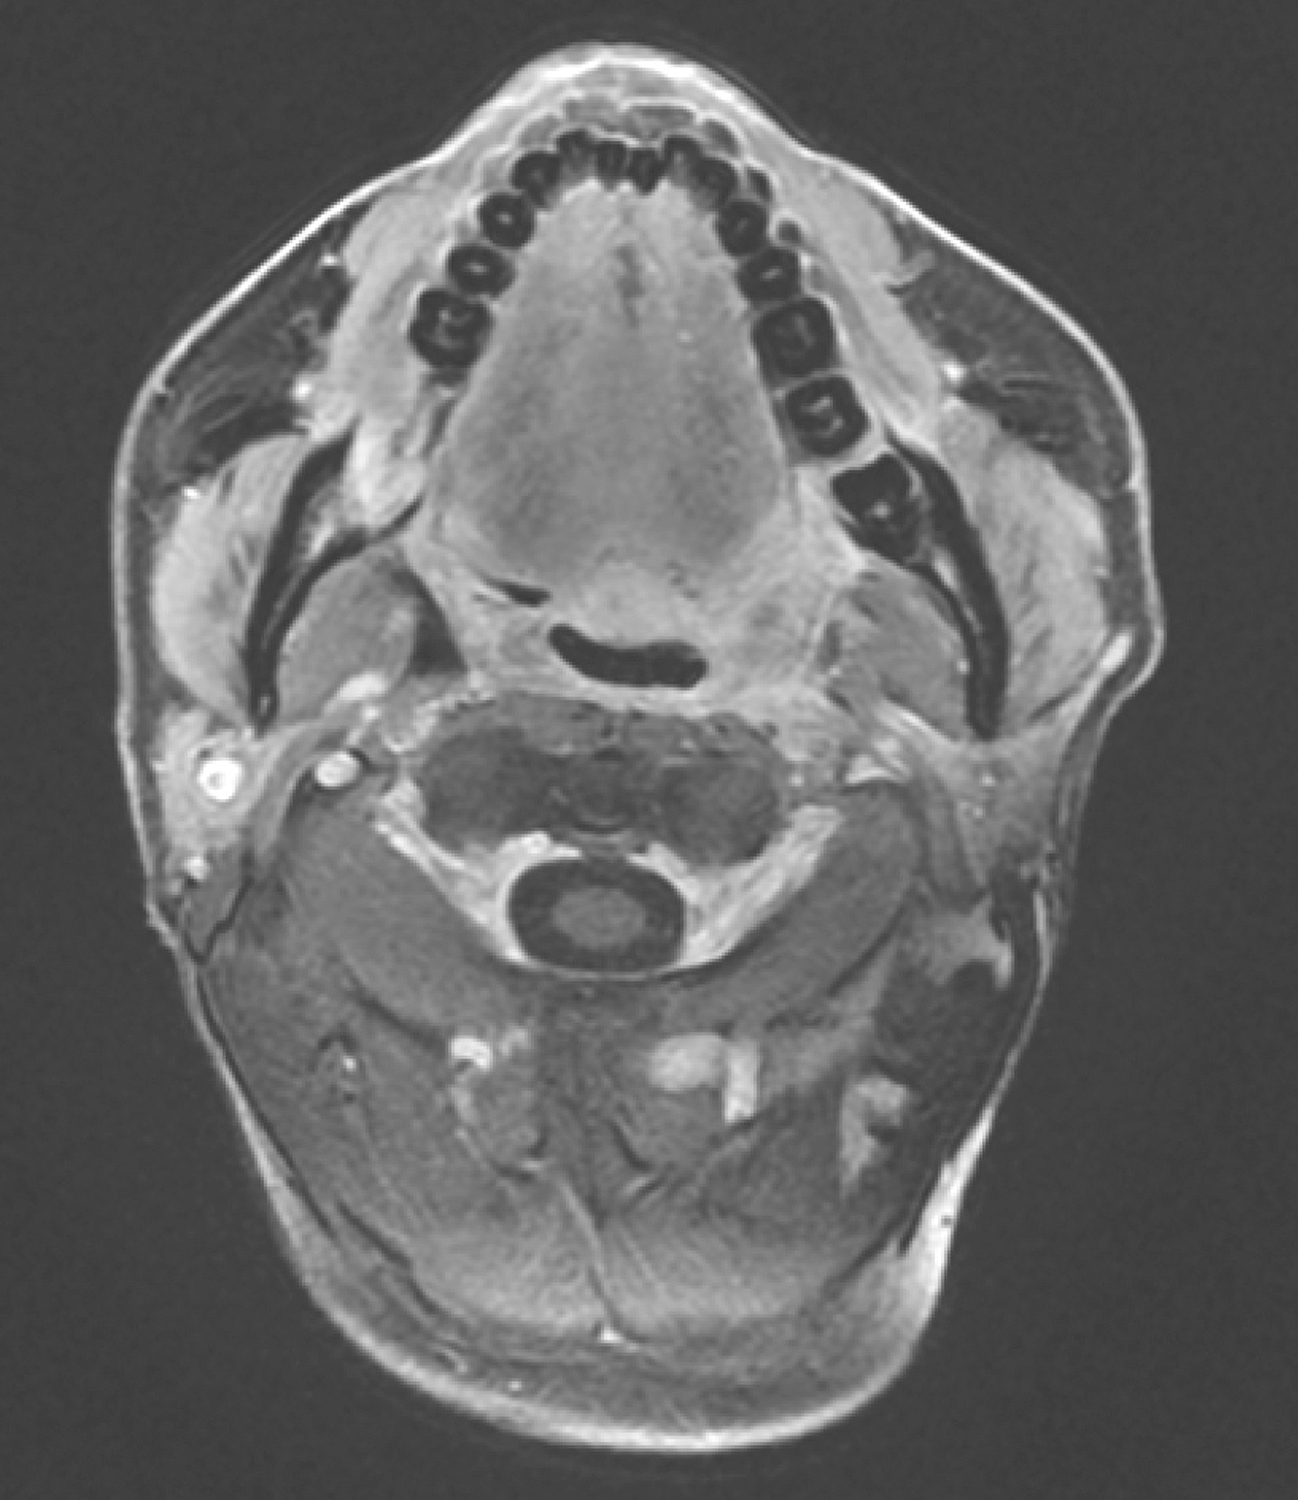

2)2017年1月12日口腔MRI检查:

“口咽癌同步放化疗中”复查,与2016年12月13日MR图像比较,口咽左侧壁肿物较前缩小,现大小约1.5cm×1.0cm,T2WI/FS呈稍高信号,增强扫描不均匀强化,肿物向外侵犯左侧咽旁间隙及左侧翼内肌,向下与左侧扁桃体关系密切(图9),请继续随诊。双侧颌下、颈深多发淋巴结,大者短径约0.7cm,请随诊。

图9口腔MRI示口咽左侧壁肿物较前缩小